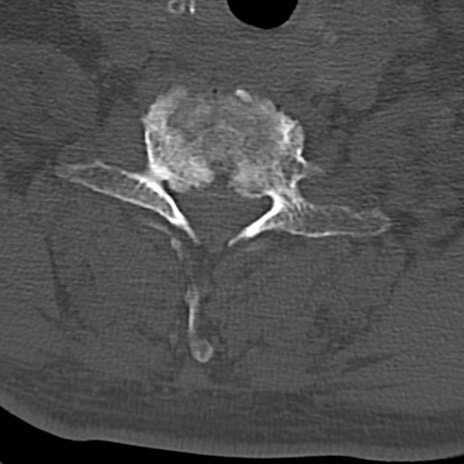

頚椎CT

横断像